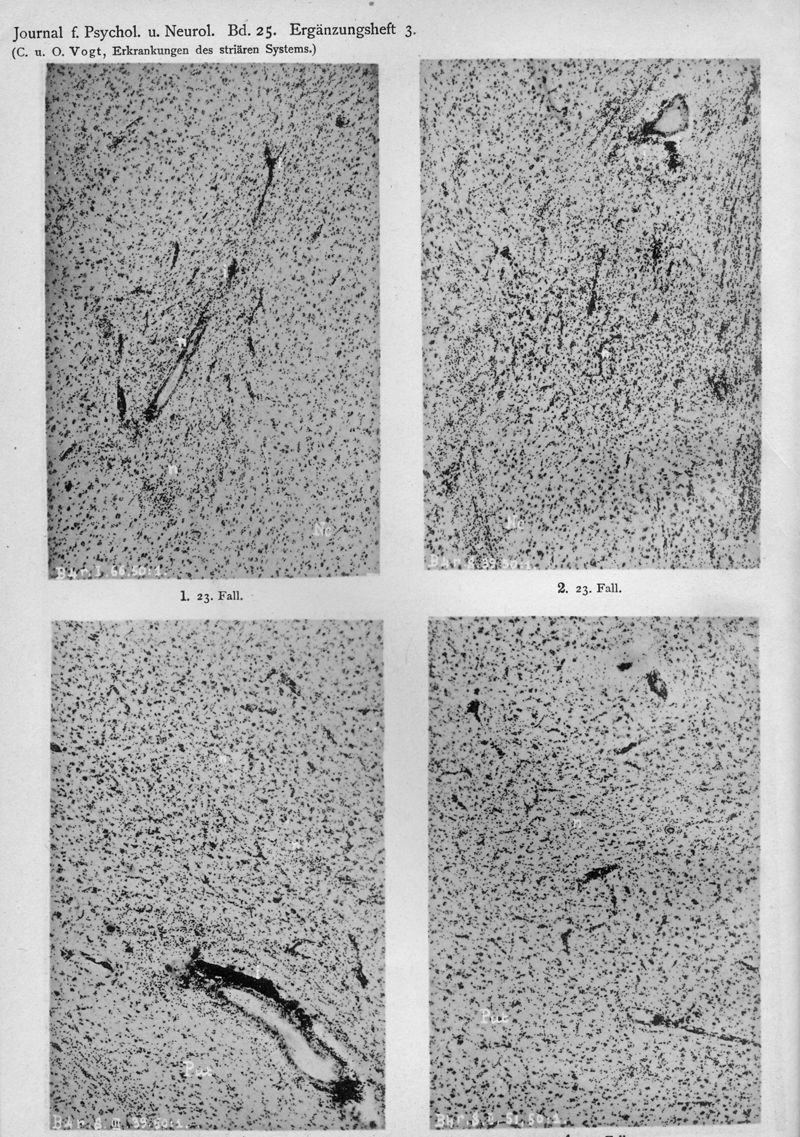

VOGT, Cécile / VOGT, O.

In : Journal für Psychologie und Neurologie,

1920, Vol. 25, pp. 627-846